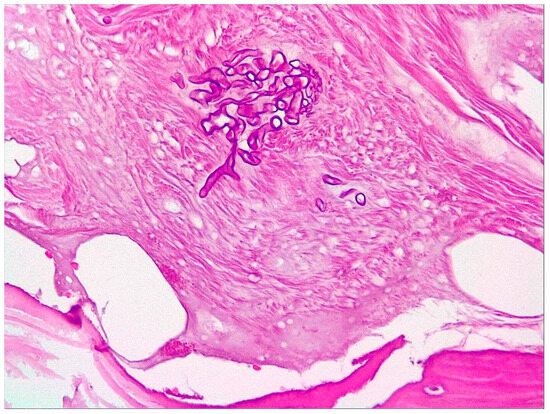

2.1. Case 1

2.2. Case 2

2.3. Case 3